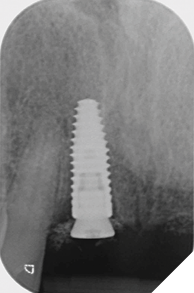

Eight weeks after extraction of the UR1 and UL2 we radiographically assessed the hard tissue healing. The soft tissues had matured well, with good volume of keratinized mucosa and we felt it appropriate to proceed with the implant placements (Figs. 8-9).

Fig. 8

Fig. 9